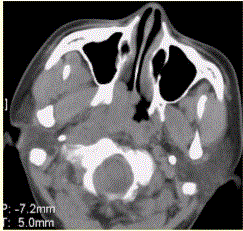

问题 患者男,45岁,鼻塞、涕中带血2周。查体颈部淋巴结增大。专科检查发现,鼻咽腔黏膜肿胀,左侧咽隐窝消失。CT表现如下图。 关于鼻咽癌,表述正确的是

选项 A.以鳞癌居多 B.早期可表现为鼻咽侧壁平坦、僵直、咽隐窝消失 C.常伴囊变或钙化 D.注射对比剂后,肿瘤呈轻度强化 E.对骨的侵犯可为单纯性骨破坏、骨质硬化或两者兼有 F.病变常沿颅底孔道侵犯

答案 ABDEF